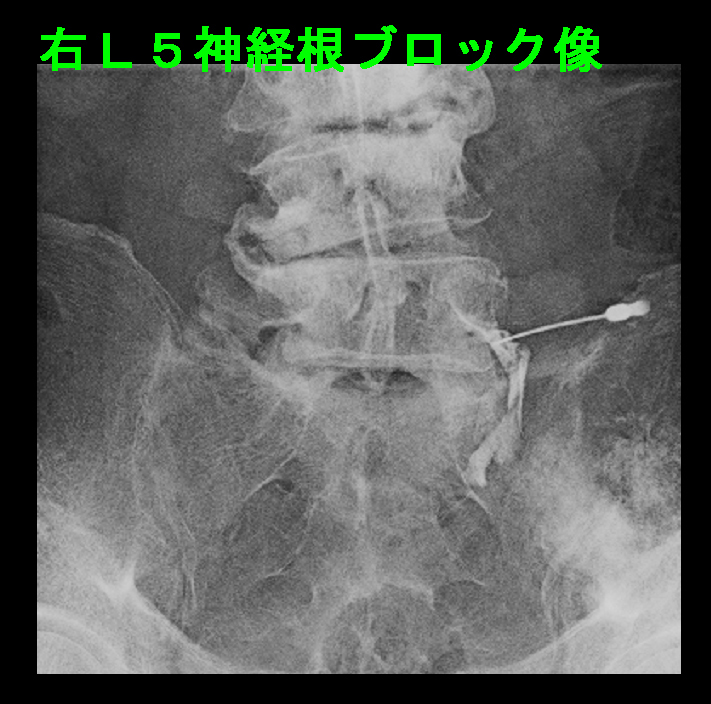

L34に中等度~重度の、L45に重度の、L5Sに中等度~重度の脊柱管狭窄の所見が確認され、L45に起因する症状と判断し、右L5神経根ブロックを施行しました。

74才男 Xp3.jpg